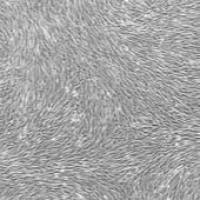

moderately high-fat diet extends lifespan in male rats and Drosophila 的研究成果 (2)。该项研究发现等热量中等高脂饮食(IHF)能通过降低游离脂肪酸(FFA)延长雄性大鼠和果蝇的寿命,并提出一种由 FFA 调节的新型衰老机制。图片来源:Cell Metabolism研究内容1. 等热量中等高脂肪饮食(IHF)显著延长雄性大鼠的寿命和健康寿命三组 Wistar 大鼠分别饲喂正常饲粮、中等高脂肪饲粮 (IHF) 和高脂肪饲粮 (FHF)。经过两年